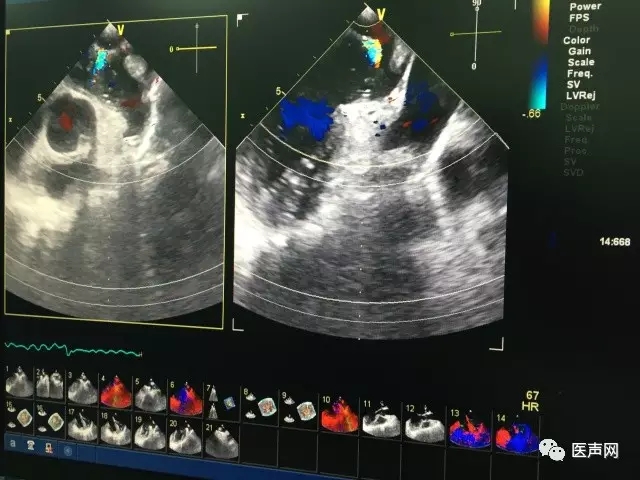

术前食道超声